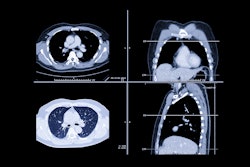

Wang's team sought to clarify whether chest CT imaging data -- specifically images from the fourth thoracic vertebra (T4HU) -- could opportunistically help predict patients' hip fracture risk in patients via a study that included 472 individuals who had both bone mineral density testing and chest CT between January 2021 and January 2024. Study participants were divided into a healthy control group and a hip fracture group. The researchers developed a predictive model based on the CT and PMI findings and assessed its efficacy using the receiver operating characteristic (ROC) curve.

"Studies have demonstrated that the … CT value of vertebrae is closely related to bone mineral density and fracture," it wrote. "This means that the CT value can be used to assess the bone mass of patients and predict fracture risk."